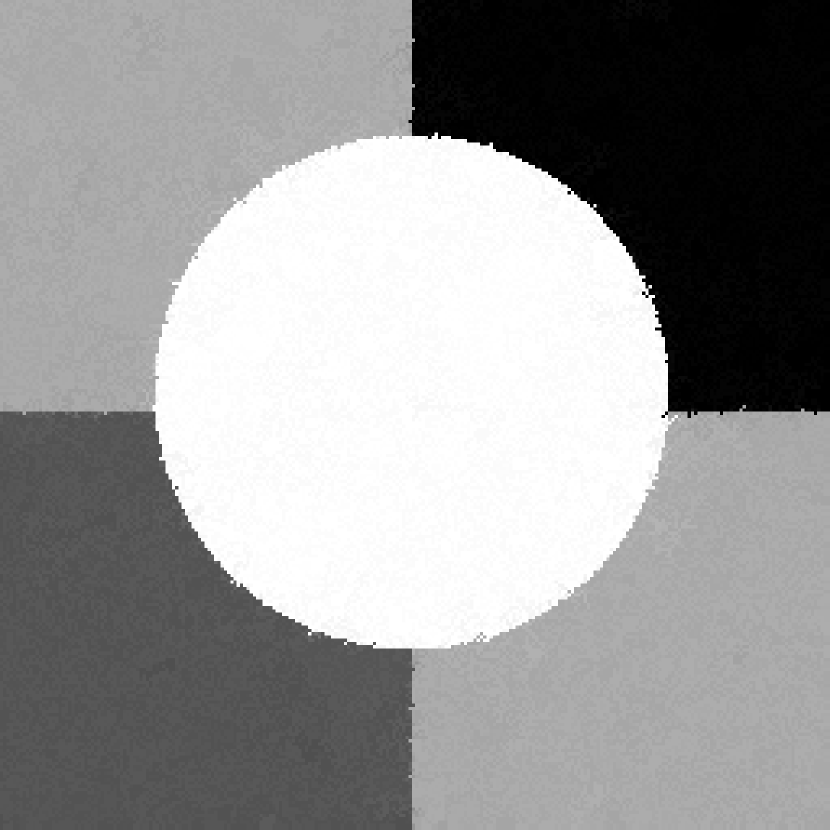

In the second experiments, we segment two medical images coming from a simulated brain database (BrianWeb): http://www.bic.mni.mcgill.ca/brainweb/. The two images are generated by T1 modality with slice thickness of 1mm resolution, 9% noise and 20% intensity non-uniformity. Here, the two images are represented two slices in the axial plane with the sequence of 100 and 110. Moreover, there are golden standard segmentations in the dataset. We set the numbers of clusters to 4. The visual comparisons are illustrated in Figs. 6 and 7.

Refer to caption

Figure 7: Segmentation results for the second medical image. From (a) to (l): ground truth, noisy image and results of FCM_S1, FCM_S2, FGFCM, FLICM, KWFLICM, ARKFCM, FRFCM, WFCM, DSFCM_N, and LRFCM.

By focusing on the marked red square in Figs. 6 and 7, we easily find that FCM_S1, FCM_S2, FGFCM and ARKFCM are sensitive to noise. FLICM and KWFLICM are vulnerable to severe intensity inhomogeneity. FRFCM brings overly smooth results due to the use of gray level histograms. WFCM and DSFCM_N cause several contours to change. However, LRFCM acquires clear contours and suppresses noise adequately. Moreover, we find that the segmentation result of LRFCM is closer to ground truth.